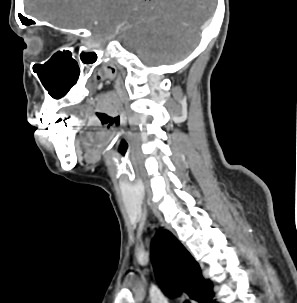

Оптимальным методом обследования гортани и голосовых связок является мультиспиральная компьютерная томография. Метод позволяет подробно визуализировать состояние данной анатомической области и выявить патологические изменения, которые незаметны при ларингоскопии (визуальный осмотр гортани с помощью специальных инструментов), проведении УЗИ и обычной рентгенографии.

Компьютерная томография позволяет оценить состояние костного скелета гортани и особенно важна в оценке состояния хрящей гортани, которые лучше всего визуализируются с помощью данного исследования. В частности, мультиспиральная КТ позволяет выявить распространение рака гортани в ткань щитовидного хряща и другие окружающие структуры.

При подозрении на опухоль гортани нативная мультиспиральная КТ дополняется проведением внутривенного болюсного контрастирования. Для этого пациенту внутривенно вводится контрастный препарат на основе йода.

Контраст хорошо накапливается в патологически измененных участках, за счет этого становятся отчетливо видны на снимках их границы, размеры, точная локализация относительно окружающих здоровых тканей. По характеру накопления контраста можно отличить доброкачественные опухоли от злокачественных, определить степень распространенности процесса, выявить поражение регионарных лимфатических узлов.

На полученных снимках можно оценить состояние всех структурных элементов гортани, голосовых складок, хрящей, а также лимфатических узлов, сосудов и шейных позвонков на исследуемом уровне. Инновационные возможности аппаратов позволяют построить 3D-модель зоны исследования, которая дает наглядную картину пространственного расположения органов, что бывает особенно важно при планировании хирургических операций.